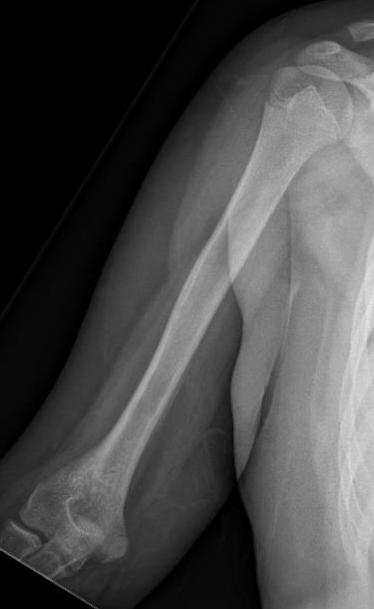

Xray

Often diaphyseal

- diffuse permeative destruction

- can be subtle

Periosteal reaction

- Codman's triangle / onion skinning / sunburst appearance

Subtle periosteal reaction humerus

Ewing's femoral diaphysis, subtle on xray with large soft tissue component